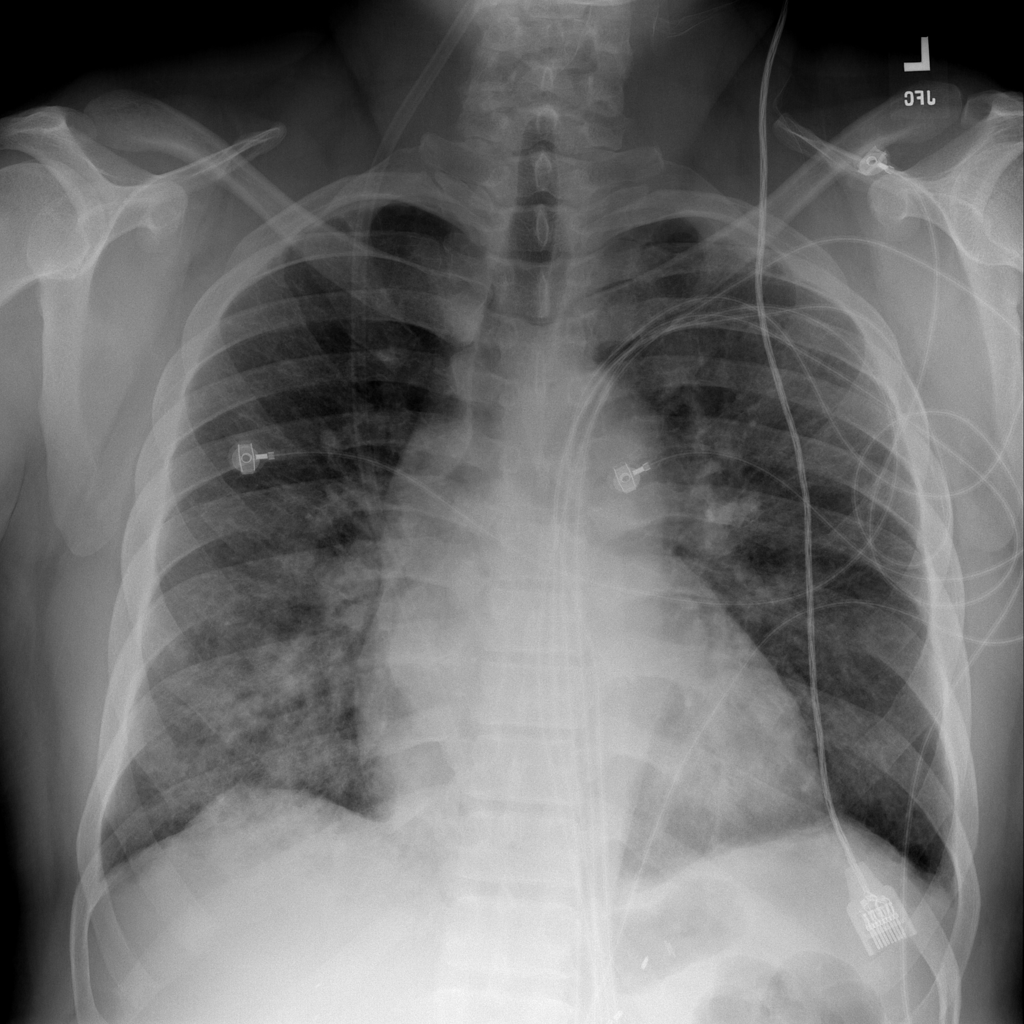

Showing up to 90 reference images for Edema.

PAT-E828 · IMG-005Edema

PAT-E828 · IMG-005

AP